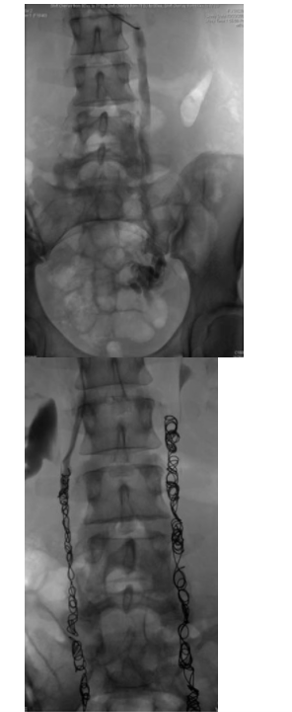

duplicated IVC

Empties into left renal vein

Can place two filters in each IVC or place a suprarenal filter